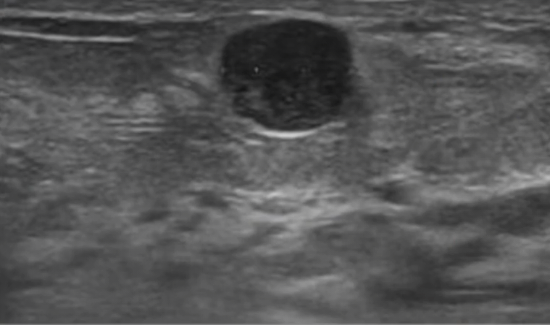

Q

BIRADS 3

BIRADS 4

Conduta:

A

Biópsia